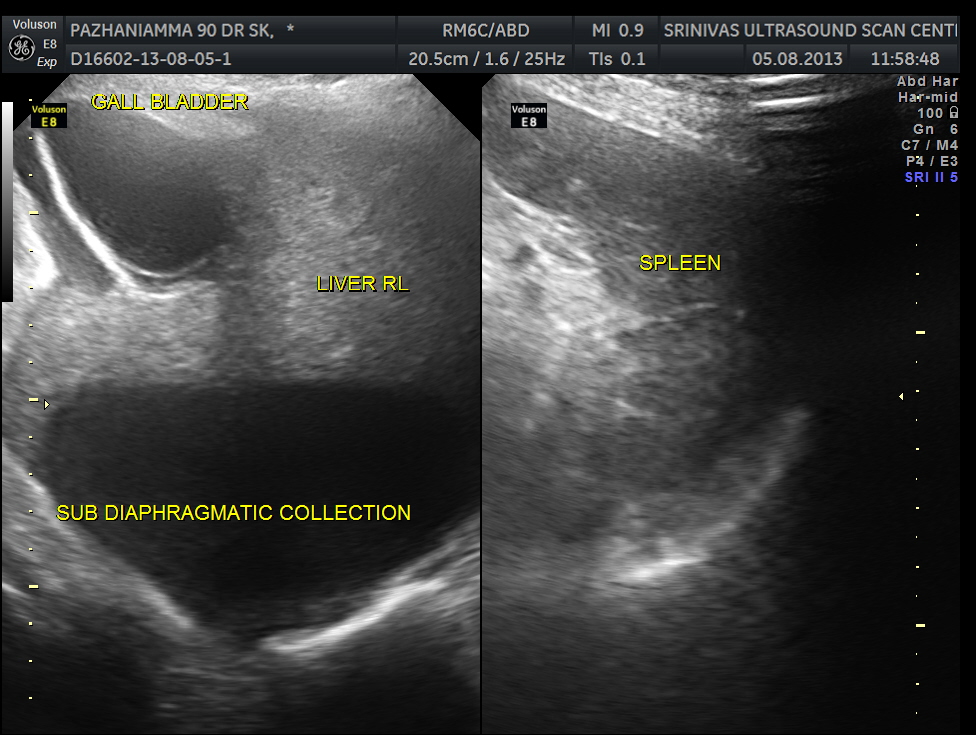

grossly distended gallbladder , with sludge and gallstones and fluid around the gall bladder.

SUB DIAPHRAGMATIC COLLECTION , PROBABLY LOCULATED WAS ALSO SEEN. MINIMAL RIGHT PLEURAL EFFUSION WAS ALSO SEEN.

The diagnosis was : acute calculous cholecystitis , cystic duct stones causing a rupture and fluid collection around the GB and loculated sub diaphragmatic collection with reactive mild right pleural effusion . Endometrial fluid collection needed further evaluation.